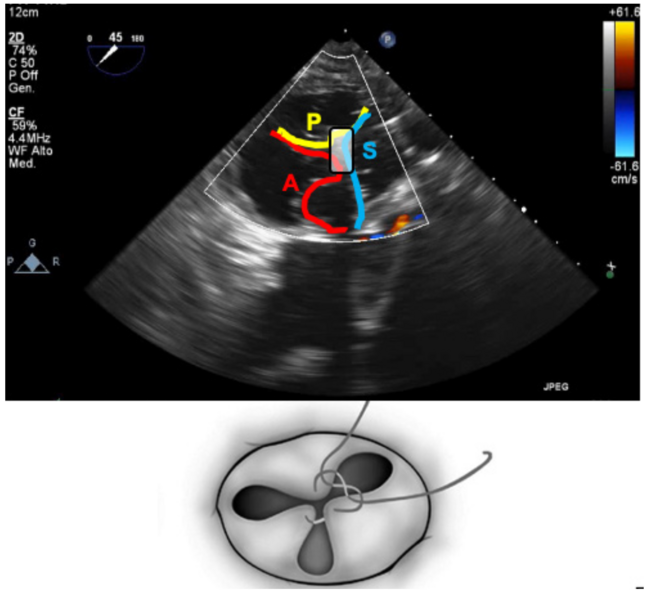

Under transesophageal echocardiography guidance, we attempted to grasp the anterior and septal leaflets. However, grasping was not initially successful. The clip was moved and deployed centrally, spanning the septal leaflet on one side and anterior and posterior leaflets close to the anteroposterior commissure on the other (Figure 1). Tissue grasping was checked and confirmed. Excellent final result was obtained with triple orifice creation (Figure 2) and mild residual regurgitation (Video Series).

To the best of our knowledge, this is the first report of simultaneous grasping of the 3 leaflets during TriClip (Abbott Cardiovascular) implantation. The final valve configuration with a triple orifice (Figure 3) resembled the result of the clover surgical technique. This technique should be considered in selected cases of challenging grasping.